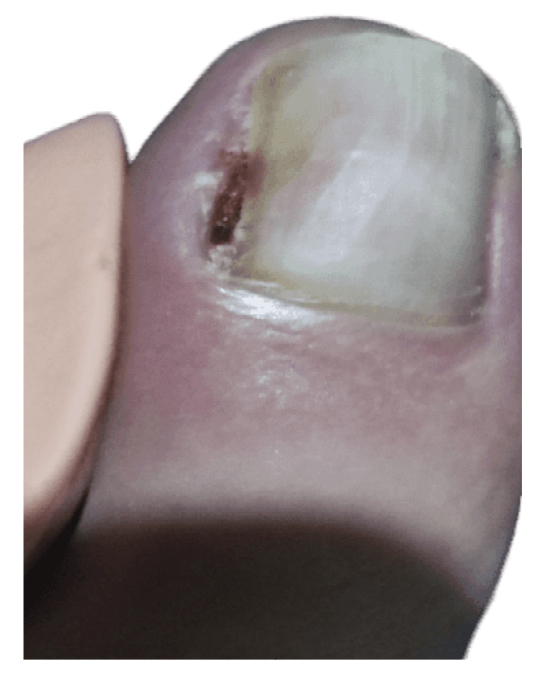

The patient initially showed improvement in pain, although it never completely subsided (Figure 4). She reported recurrence of the nail lesion, which led her to seek a second opinion 6 weeks after the intervention with another podiatrist. This latter podiatrist, on December 27th (Figure 5), performed a bacterial culture of the lesion, which turned out negative, and also evaluated the lesion by ultrasound (without report). On January 13th, the patient underwent surgery using the phenol-alcohol technique on the lateral border of the first toe of the left foot (Figure 6).

Figure 5. 16th week. Negative microbiological culture and sonograhpic assessment (not available).